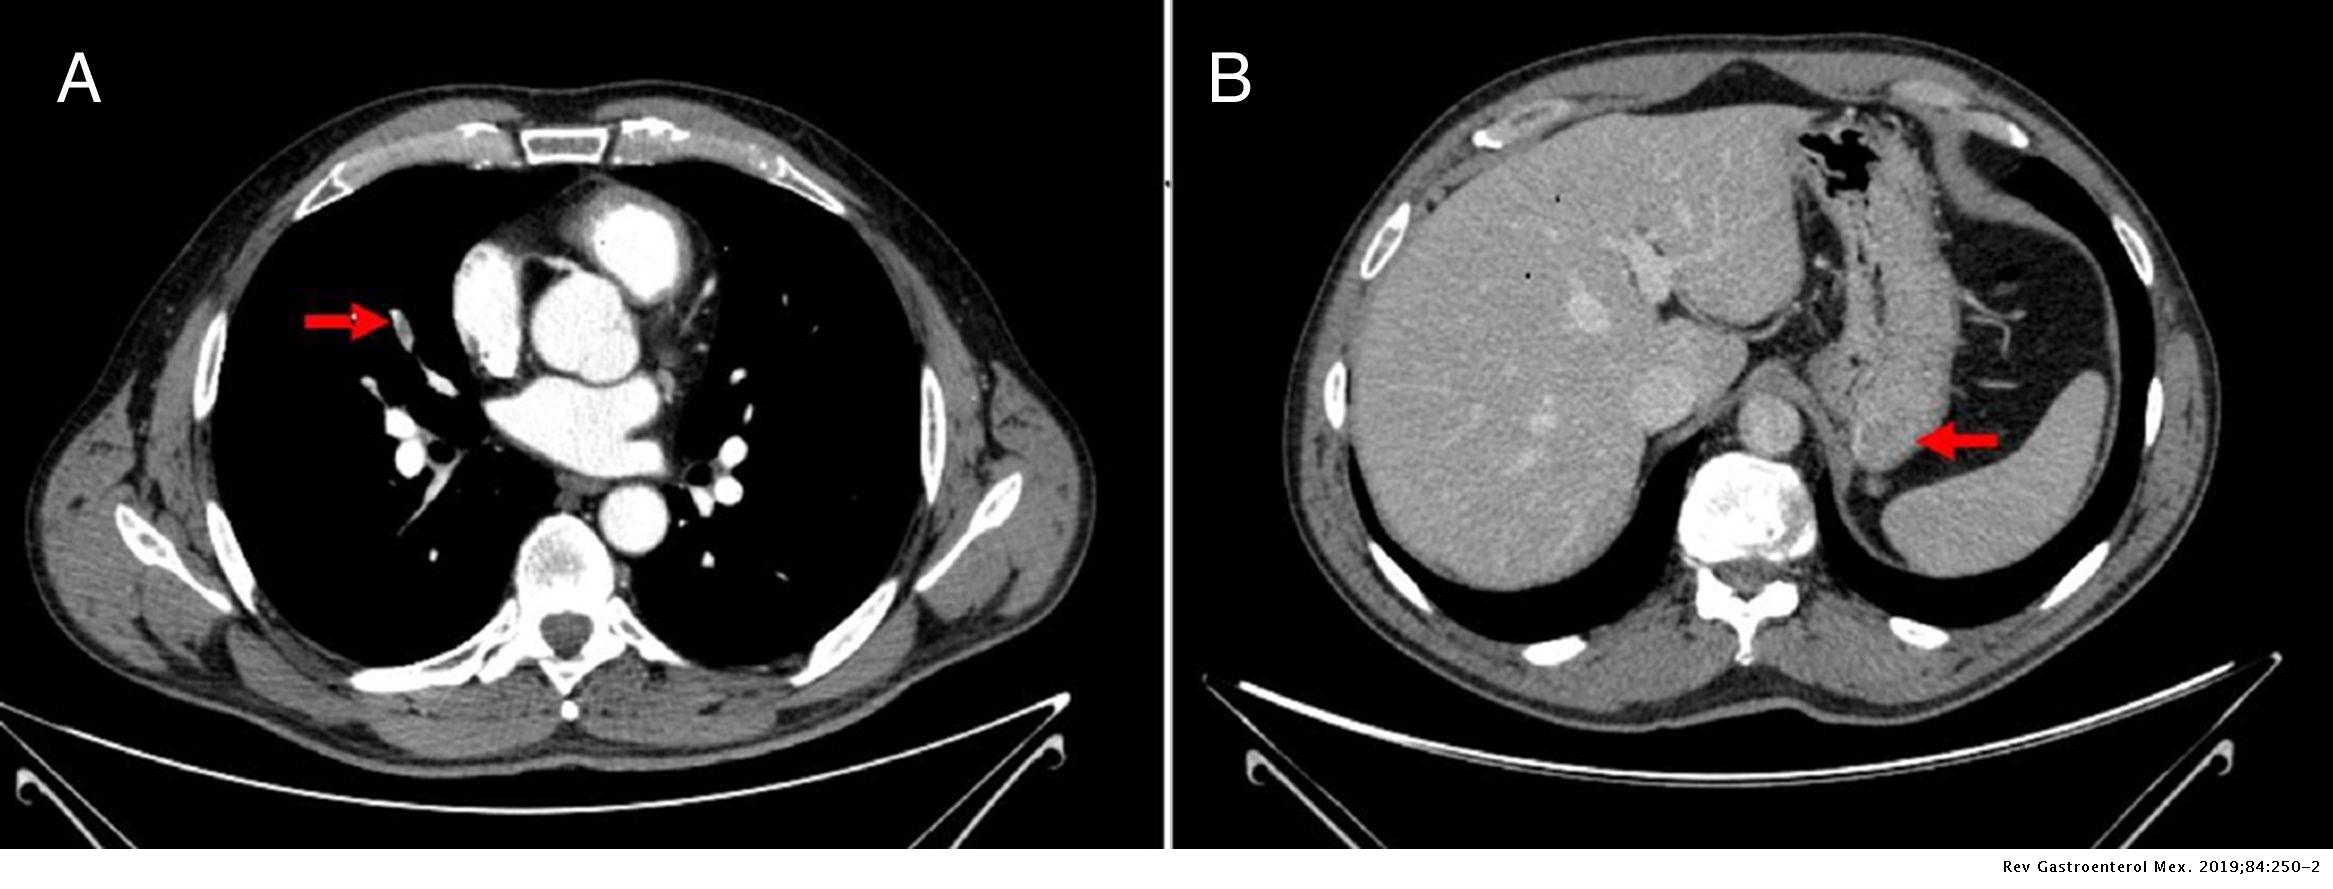

Los exámenes fluoroscópicos con bario, de las vías digestivas altas y las vías digestivas bajas (tránsito intestinal) y el TAC son los más frecuentemente usados para el diagnóstico de pacientes con dolor abdominal superior. Ambos son adecuados para hacer el diagnóstico de GIST, sin embargo los tumores pequeños pueden permanecer ocultos, especialmente en casos de exámenes poco exhaustivos.

Los GISTs pequeños aparecen como masas intramurales. Cuando crecen (> 5 cm), la mayoría de ellos, lo hacen con mayor frecuencia hacia afuera del intestino. Pueden existir calcificaciones. Cuando disminuye el aporte sanguíneo para el tumor, este puede hacer necrosis interna, creando una cavidad central llena de fluido que eventualmente puede ulcerarse en el lúmen del intestino o el estómago.

El tumor puede invadir directamente estructuras en el abdomen. El sitio más común de extensión es al hígado. Extensión al peritoneo puede ser vista. A diferencia del adenocarcinoma gástrico o el linfoma gástrico o de intestino delgado, las adenopatías malignas (inflamación de nódulos linfáticos) son poco comunes (<10%).